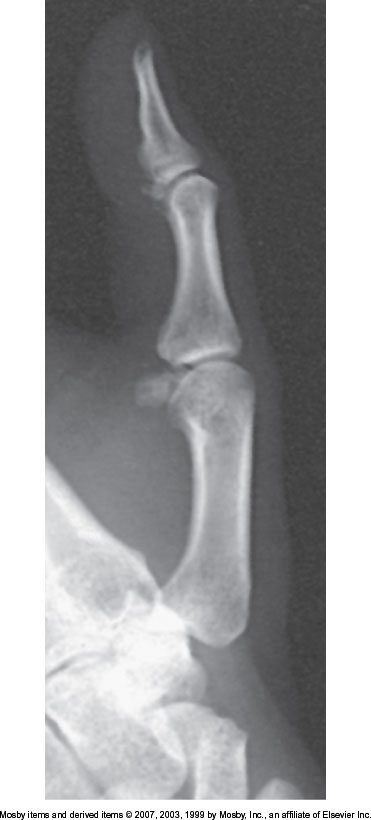

What position is demonstrated?

Lateral Finger